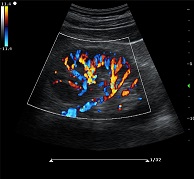

? ?● 多種成像模式

? ? ? ?B、C、PW、CW、BCD三功、大角度偏轉(zhuǎn)成像、實(shí)時(shí)寬景成像、梯形成像(僅支持線陣)、解剖M型、彩色M型成像、組織多普勒成像、3D/4D成像

? ?● 彩色多普勒增強(qiáng)技術(shù)

? ? ? ?有效抑制彩色血流閃動(dòng)噪聲,提高血流分辨率和靈敏度